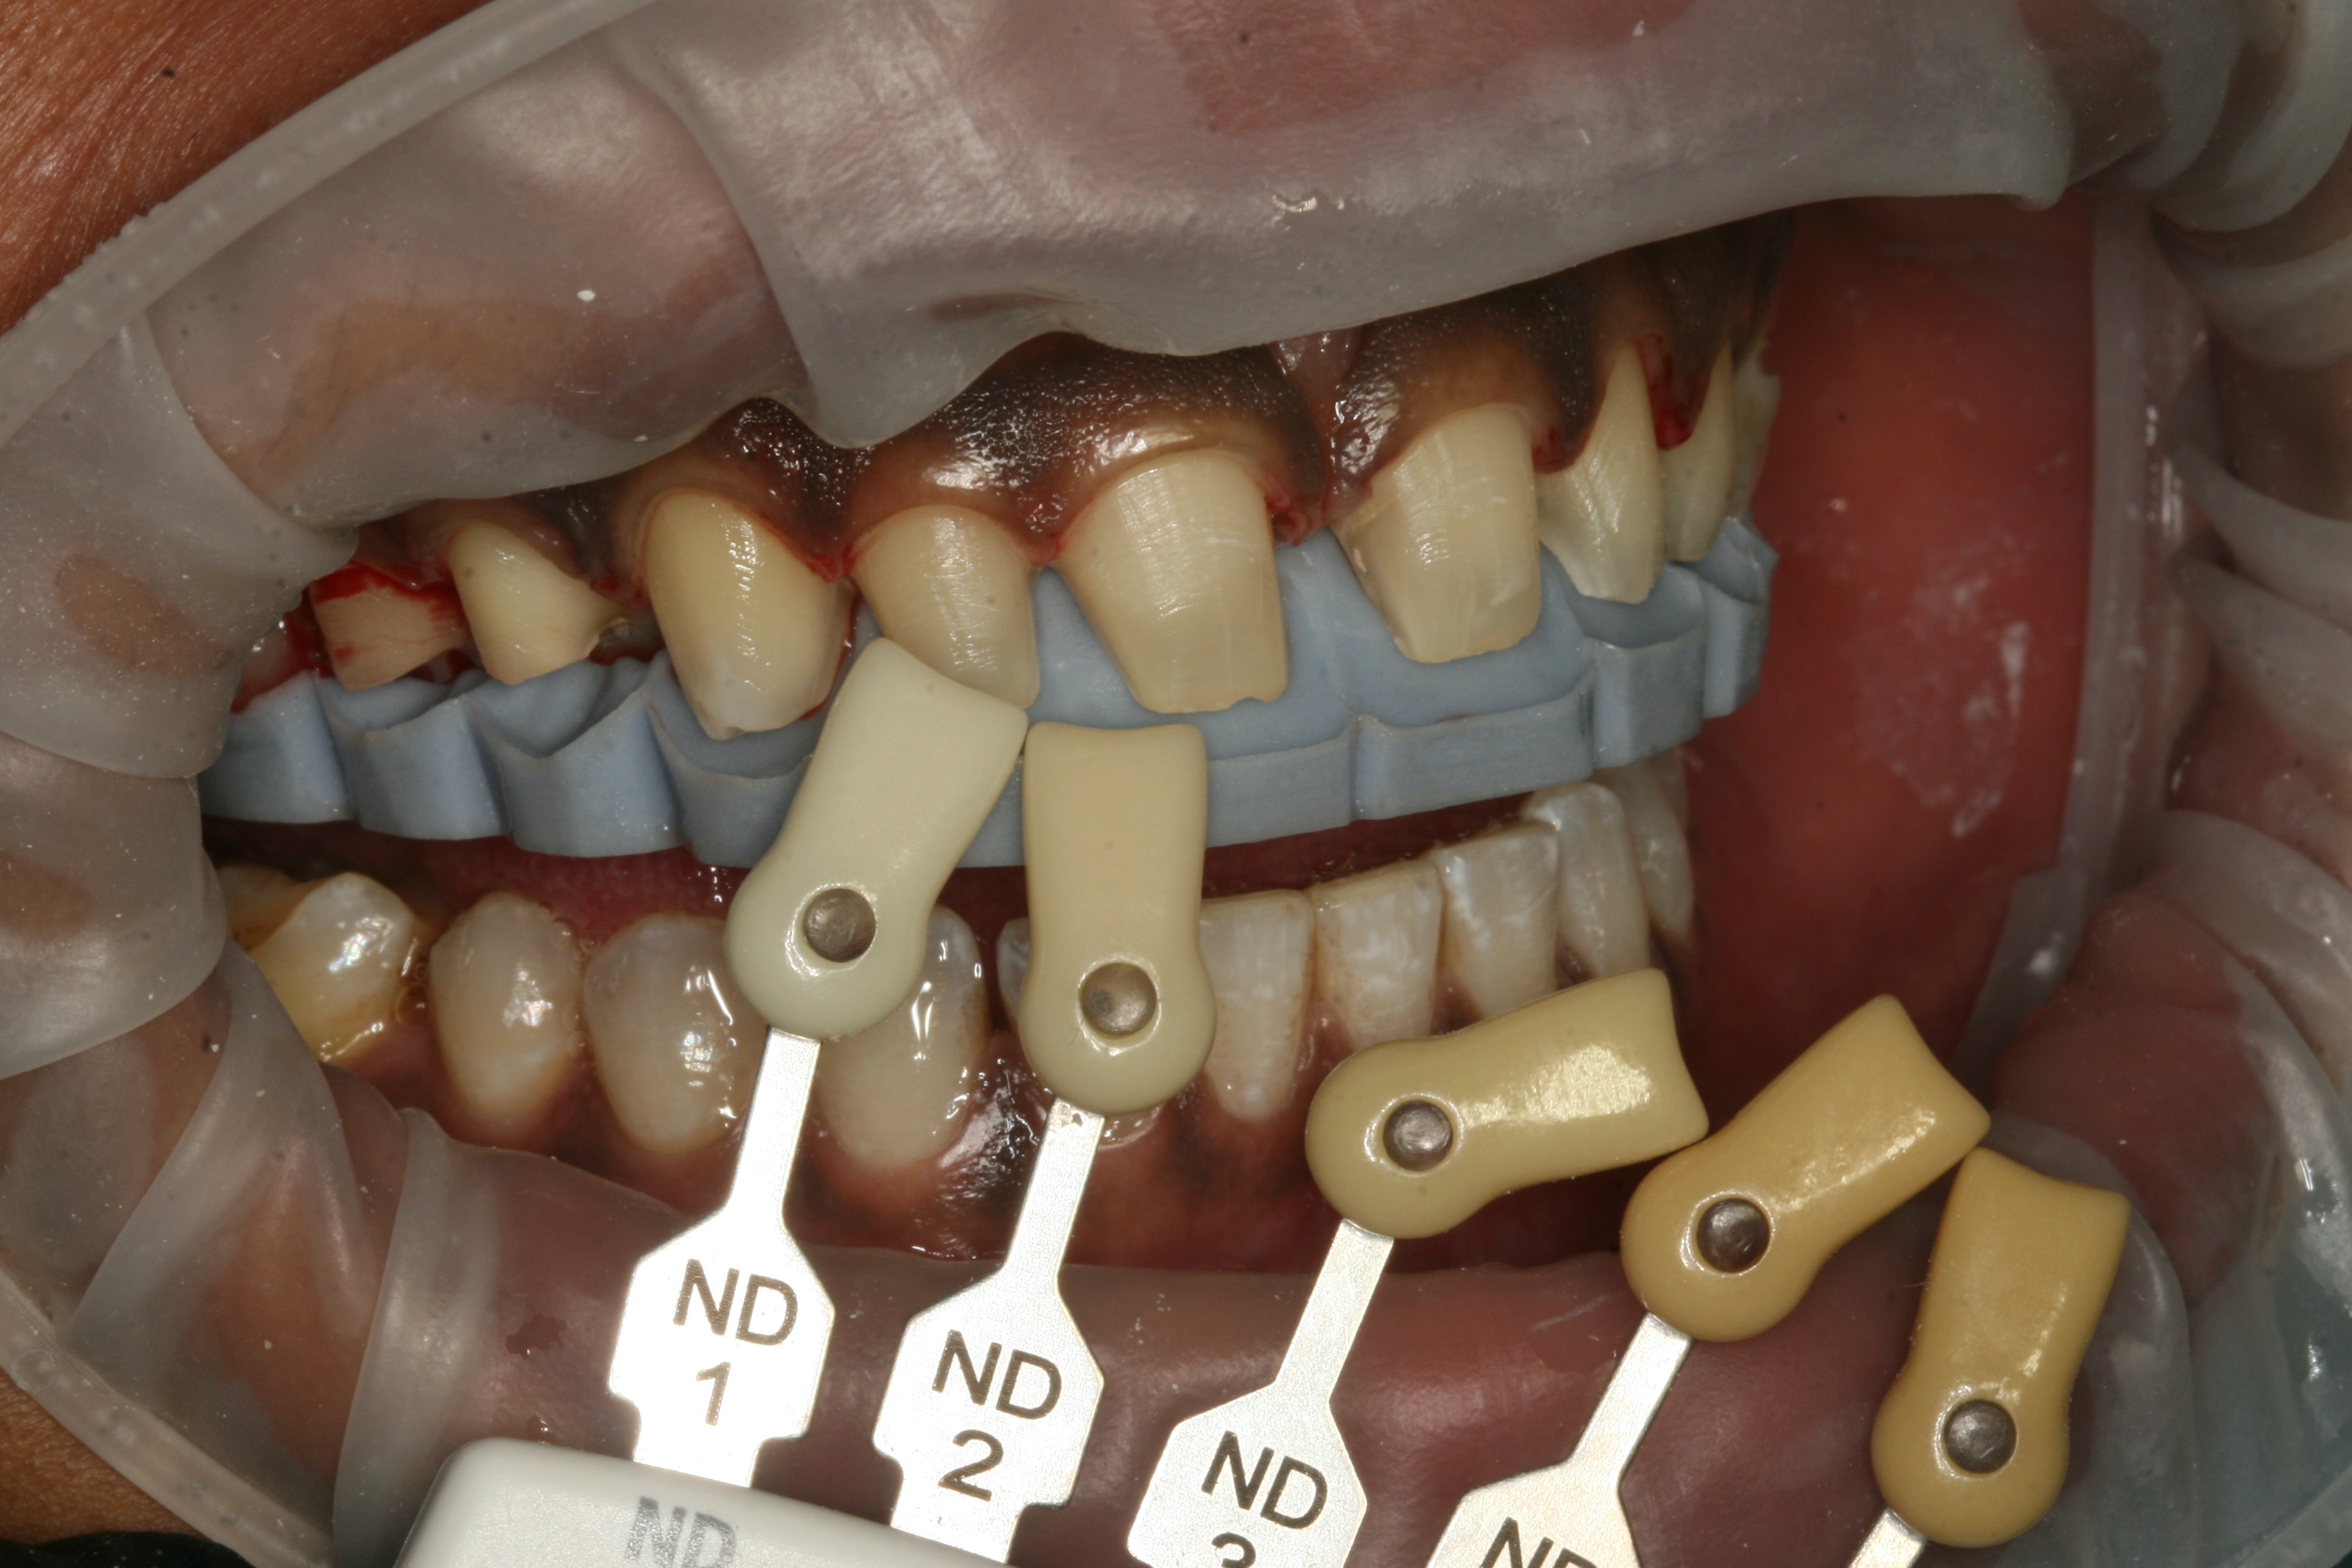

On her next visit, the patient was able to view and approve the diagnostic wax-up presented on mounted study models prior to any preparation of her teeth.6, 7 Under colour-corrected lighting, digital photographs were taken from multiple angles with at least two shade tabs per photograph to assist in shade matching and colour mapping (hue, chroma and value) prior to any dehydration of the teeth.6, 7 The patient again stressed her desire to have her definitive veneers be slightly lighter in shade than her mandibular teeth but to blend in with her natural dentition. This was noted for laboratory communication purposes.

Initial tooth preparation was com­pleted with a 2000.10 Two Striper super-coarse grit diamond bur (Premier Dental) in a high-speed handpiece under copious wa­ter spray. Owing to the diastema and posi­tioning of the patient’s teeth, some sub­gingival tooth reduction was required to develop a proper emergence profile. Ade­quate incisal (1.50 mm) and facial (0.75 mm) porcelain thickness needed to provide room for layering, slight colour change and addition of incisal effects in the por­celain were confirmed with the lingual and incisal polyvinylsiloxane stent.6, 7 A well-defined cervical margin was estab­lished with a 703.8F diamond bur (Pre­mier Dental) to provide a positive veneer stop, ensuring a smooth, cleansable, precise porcelain–tooth interface while allowing for devel­opment of a proper emergence profile.6, 7 Photographs of the preparations were taken, and a preparation shade of ND 2 (Ivoclar) was recorded (Fig. 3). Expasyl gingival re­traction paste (Acteon Group) was expressed around all the gingival margins and allowed to sit for a period of 3 minutes to provide haemostasis and adequate tissue reflection. After 3 minutes had passed, the paste was rinsed away with a copious, forceful water spray. The preparations were lightly dried, and a master impression was taken with Honigum Pro Light and Heavy im­pression material. A Futar D stick bite of the prepared teeth in centric occlusion was taken and photographed.

Fig. 4: Planned tooth shade.

Fig. 5: Shade comparison with the opposing dentition.

The 24-hour post­operative check ap­pointment was particularly important because it allowed the patient to express feedback based on self-analysis of the proposed shapes and contours of her new smile. The patient reviewed and ap­proved the shape of her provisional res­torations and the shade tabs selected at the prior appointment. Proper phonetics, occlusion and anterior guidance were confirmed. A few minor adjustments to her occlusion on the lingual aspect of the provisional res­torations were required. Photographs of the approved provisional restorations and shade tabs were taken (Figs. 4–6). Other provisional records were taken, in­cluding a Futar D stick bite in centric occlu­sion and a Honigum Pro im­pression of the approved provisional restorations (Fig. 7). All the records were disinfected and sent to the ceramist, accompanied by a completed laboratory prescription, notes and all the photographs taken to that point. The ceramist was instructed to use the impression of the approved provisional res­torations as a guide for the final shape, size and contour of the porcelain restorations.